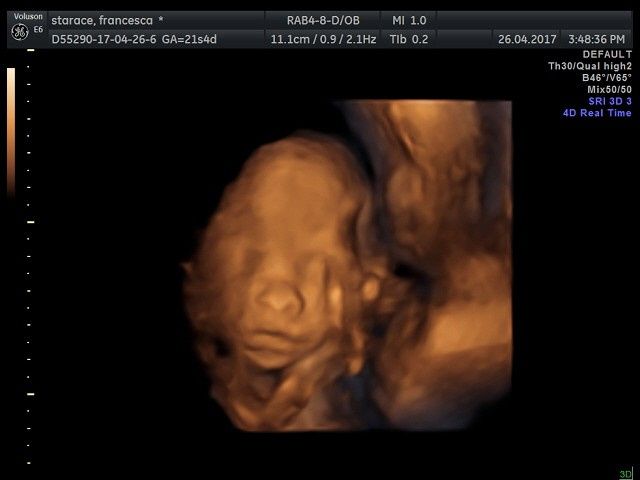

Ciao ragazze, in un attacco di insonnia vi posto le foto della morfologica in 4d di ieri😍! La polpetta sta alla grande, pesa 430 gr ed è tale e quale al papa!😂😂😂tutti questi mesi nella pancia con noi mamme, e poi sono la fotocopia dei mariti!!!😂😂😂un...